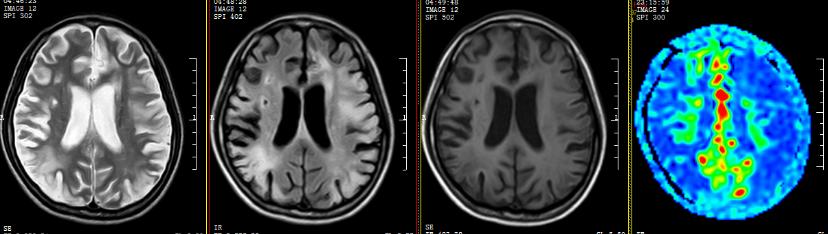

▲术前

我院ASL序列提示:双侧额颞岛顶枕叶多发片状低灌注区,以额颞顶叶低灌注较明显;DSA提示:烟雾病,双侧颈内动脉末端闭塞,颅底可见烟雾样血管生成并向远端代偿,可见右侧颈外动脉系统对颈内系统部分代偿。